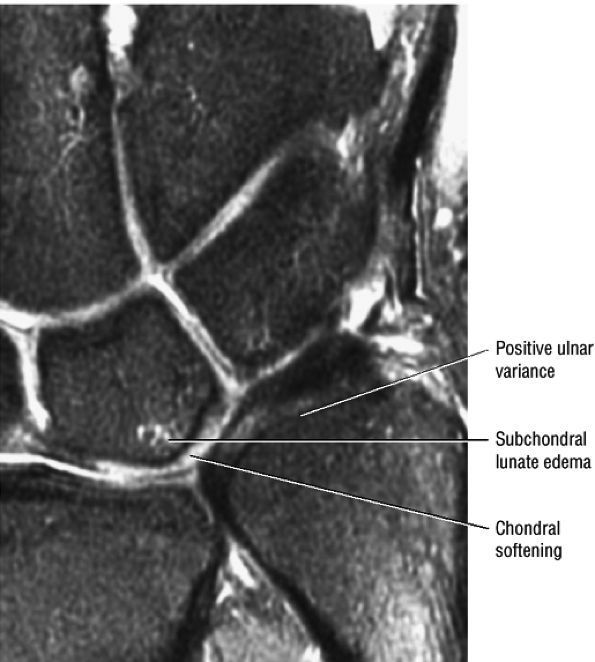

(ulnolunate) impaction syndrome, whereas ulnar negative variance may be associated with Kienböck's disease of the lunate. With distal radioulnar joint instability, the ulna is dorsally or volarly subluxed with respect to the radius, usually due to severe TFC complex tears.